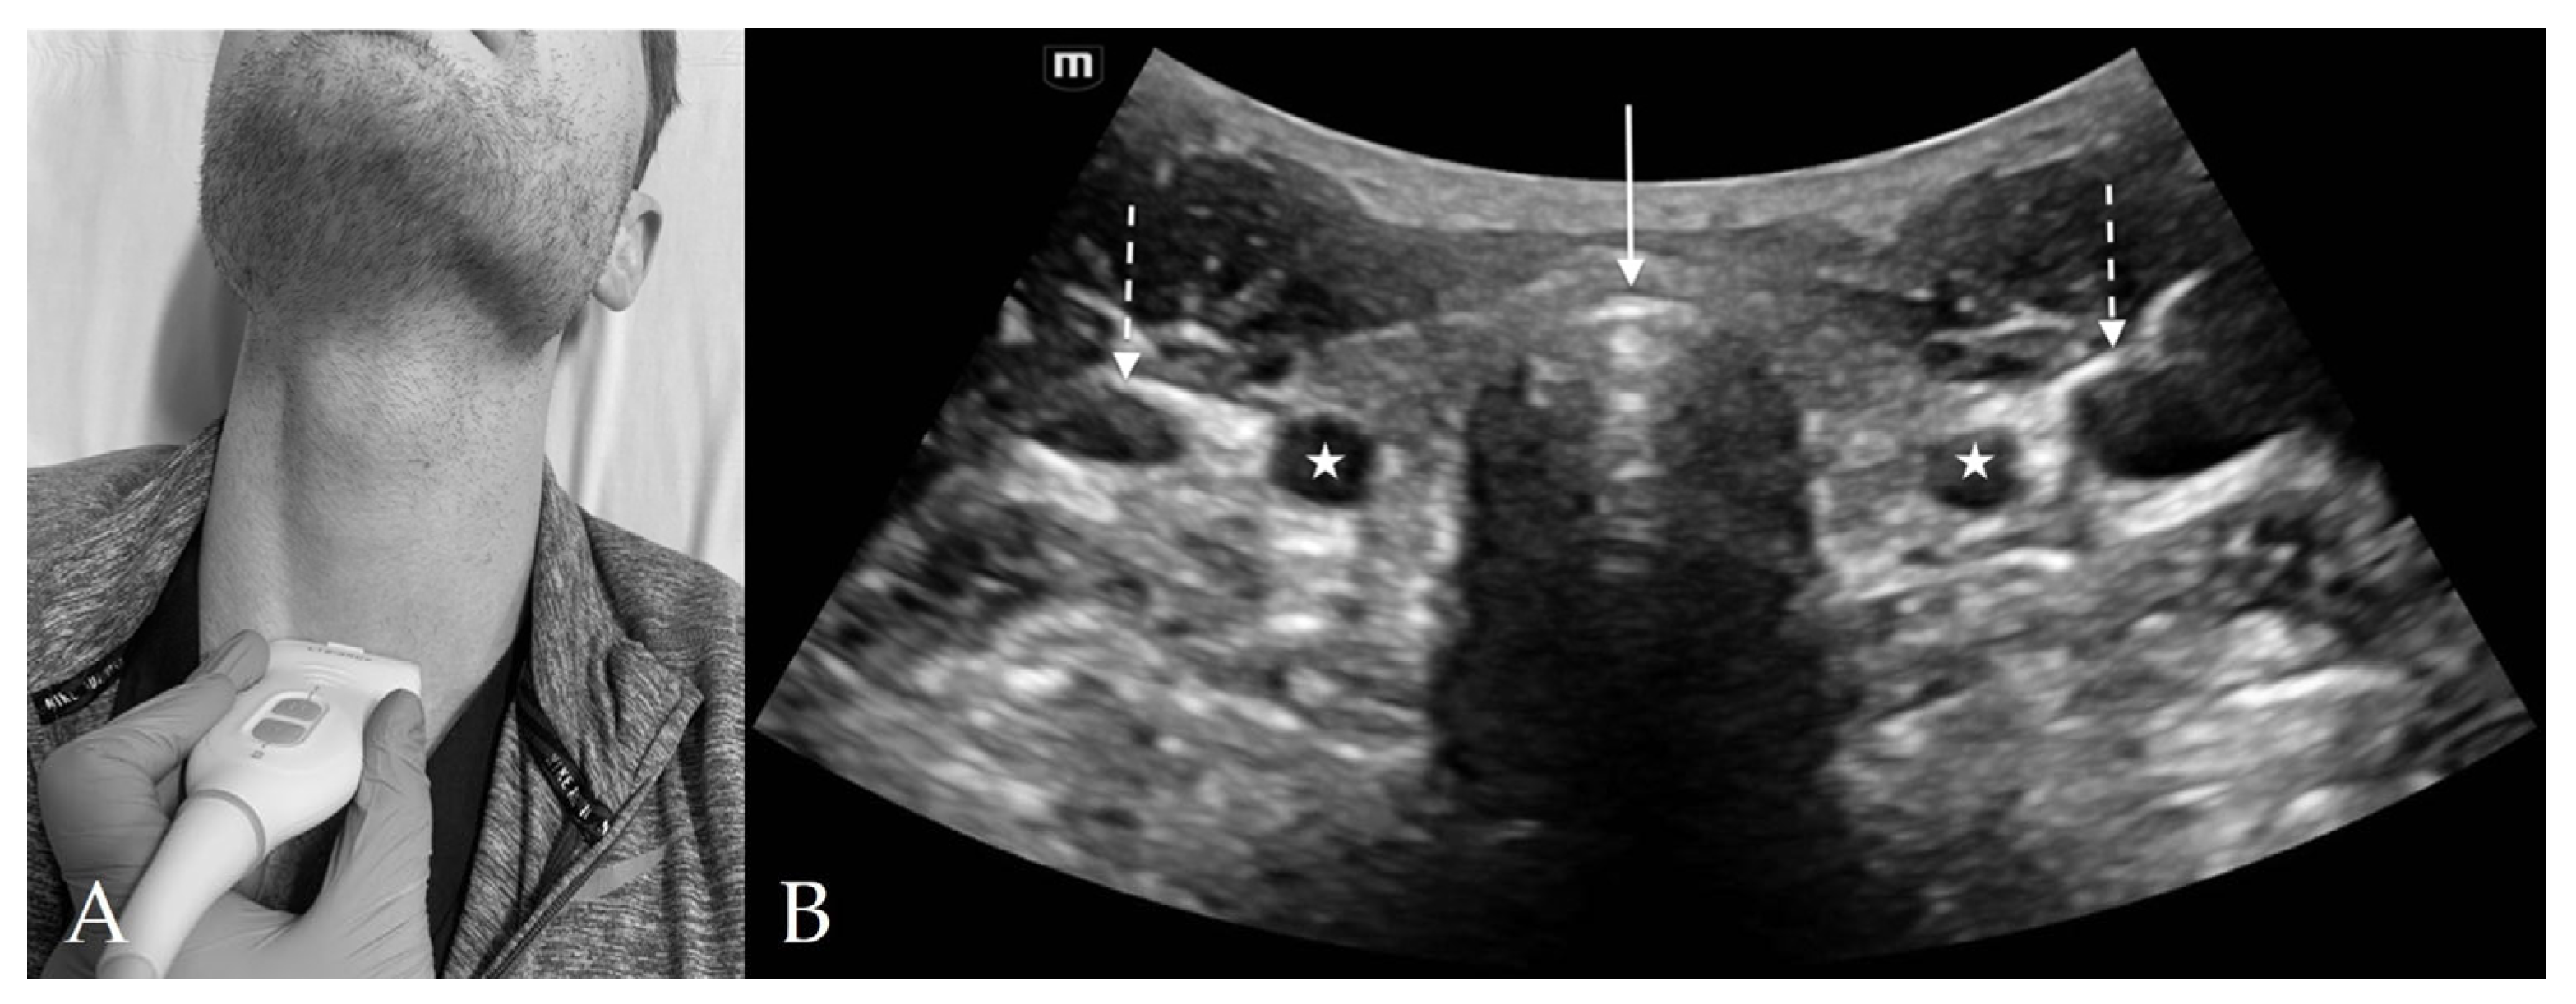

3. Probe Selection and Technique

4.3. Thyroid View

4.4. Cricothyroid View

4.5. Suprasternal View